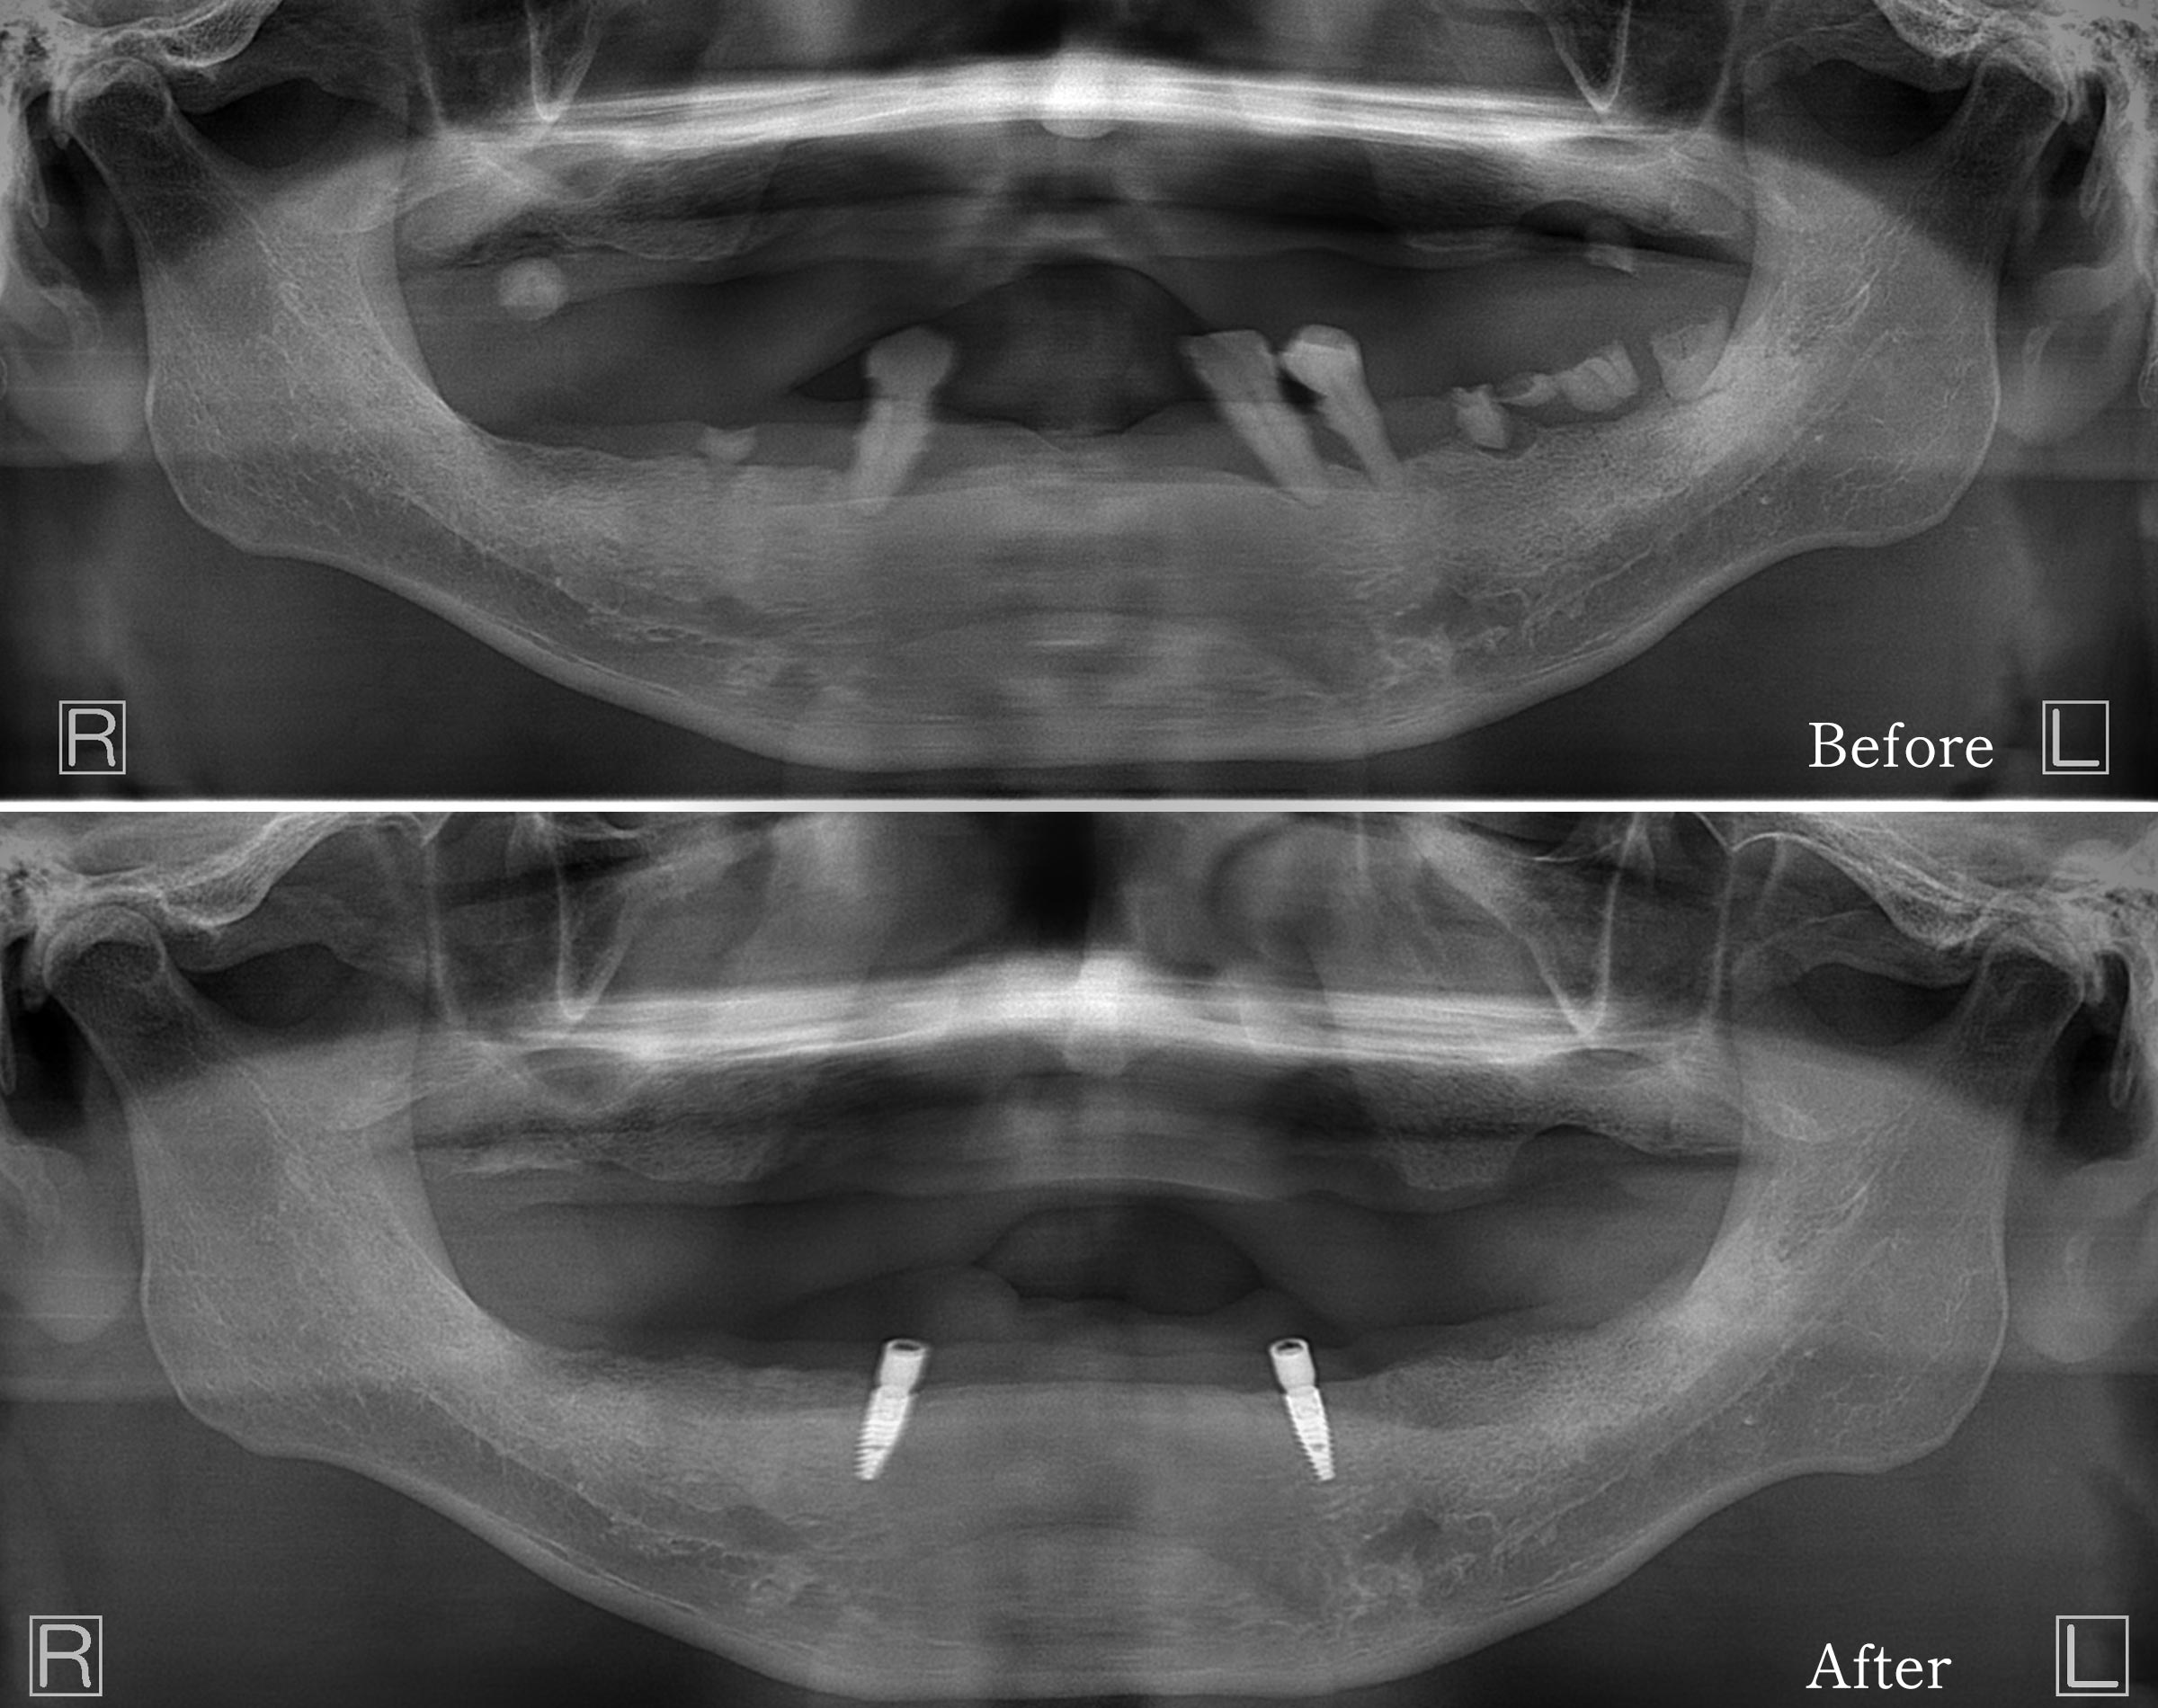

• CT検査:前歯のあたり(犬歯間)の骨は十分に残っており、インプラント2本の埋入が可能

下あごの残存3本の歯を抜歯し、そのままの部位に2本のインプラントを即時埋入しました。手術時間は約1時間程度で、出血や腫れも少なく経過しました。

3か月ほど経過を観察し、インプラントが骨と安定的に結合したことを確認。その後、見た目・咬み合わせ・発音などをさらに整えた最終のロケーターデンチャーを作りました。